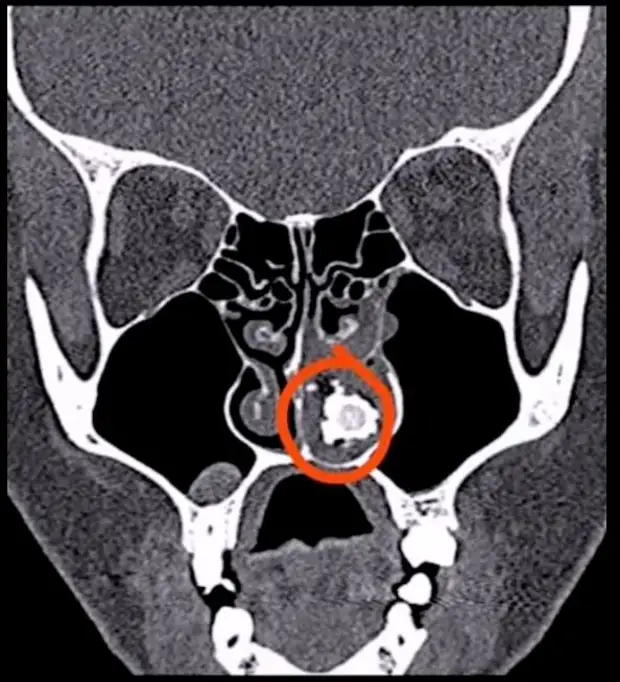

Ринолит это